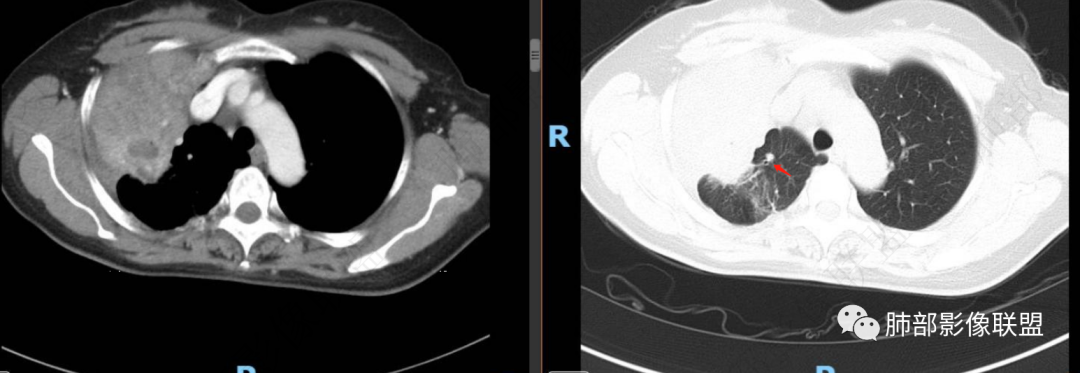

两个病灶独立,又有关联性,内侧病灶近端的支气管包绕在外侧病灶之中,但是走形自然

无堵塞迹象,支气管壁弥漫增厚

腔通畅

内部大片坏死区,其中还有不规则空洞

坏死腔内壁清,有强化环

肺动脉在实变区走形自然,坏死腔周围受压推移,走形自然,坏死区内破坏

1、中央型肺癌:腔内为主——堵塞,不符合,支气管还是通畅的;腔外为主,不符合,会在肺门区周围团块,而不是远端

2、外朝内蔓延的恶性肿瘤:肺炎型肺癌——坏死腔内壁光滑,内部是坏死中空洞,而非假大空,放待排。癌肉瘤?不是一个类圆形团块。

支气管壁弥漫增厚,周围GGO,粘液腺癌啊GGO是靠近病灶区密度高,外围低,这一例不是很符合

这类坏死区内空洞,提示坏死液比较粘稠

不是液化坏死,液化坏死,这么大,有气体进来按理会形成液气平面

凝固性坏死